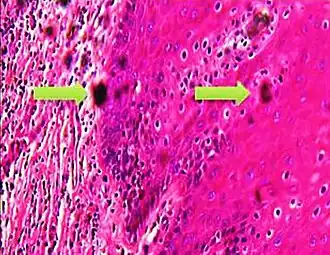

A crush artifact is an artificial elongation and distortion seen in histopathology and cytopathology studies, presumably because of iatrogenic compression of tissues. Distortion can be caused by the slightest compression of tissue and can provide difficulties in diagnosis.[2][3] It may cause chromatin to be squeezed out of nuclei.[4] Inflammatory and tumor cells are most susceptible to crush artifacts.[4]

Crush artifact from compression by forceps on the tissue sample

Folding artifacts (white arrows) and a crush artifact (black arrow, with cytoplasmic hypereosinophilia and nuclear pleomorphism) from a needle